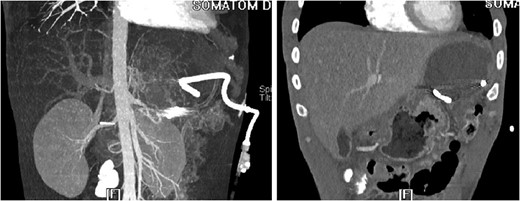

Splenic artery angiogram after placement of embolization coil showing patency of flow, no active extravasation.

3D reconstruction and coronal CT after placement of pigtail drainage catheter.